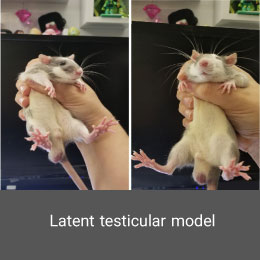

- Create and induce a variety of animal models